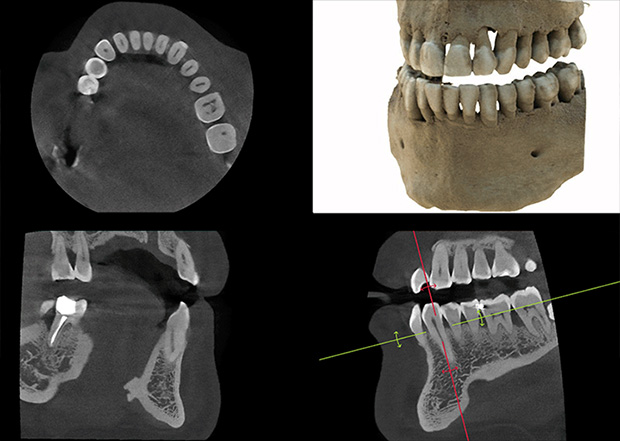

医生可从任意角度与细节观察分析

病例,优化治疗方案与计划

传统CT的二维扇形束扫描,投影数据是一维的,重建后的图像数据是二维的,经过重组的三维图像是连续多个二维切片堆积而成的,金属伪影较重。在数字化口腔诊疗的全链条中,数据精度决定治疗效果,对此,麦芽口腔采用三维锥形束X线取代扇形螺旋CT,二维的投影数据重建直接获取三维图像,牙齿或颌骨等硬组织结构成像质量更好。

3D模型,精确重建咬合

麦芽MAC数字化精确影像系统,能清晰重建并呈现颅面、牙颌咬合关系细节,是麦 芽口腔实现“以修复为导向”的基础。

3D可视呈现,优化治疗计划

麦芽MAC数字化精确影像采集,可通过全景扫描、3D面部扫描及数字化3D智能口扫 结合,为您呈现3D可视方案,以改善治疗计划。

“在疑难种植问题上,CBCT的广泛应用,突破了传统影像学技术只能用二维影像来 反映三维目标的局限,在术前诊断和手术规划过程带来了极大便利。”